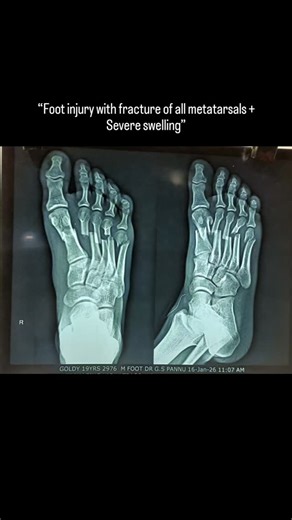

Water On Wrist Injury - Eclipse ESP

Feet - Ice